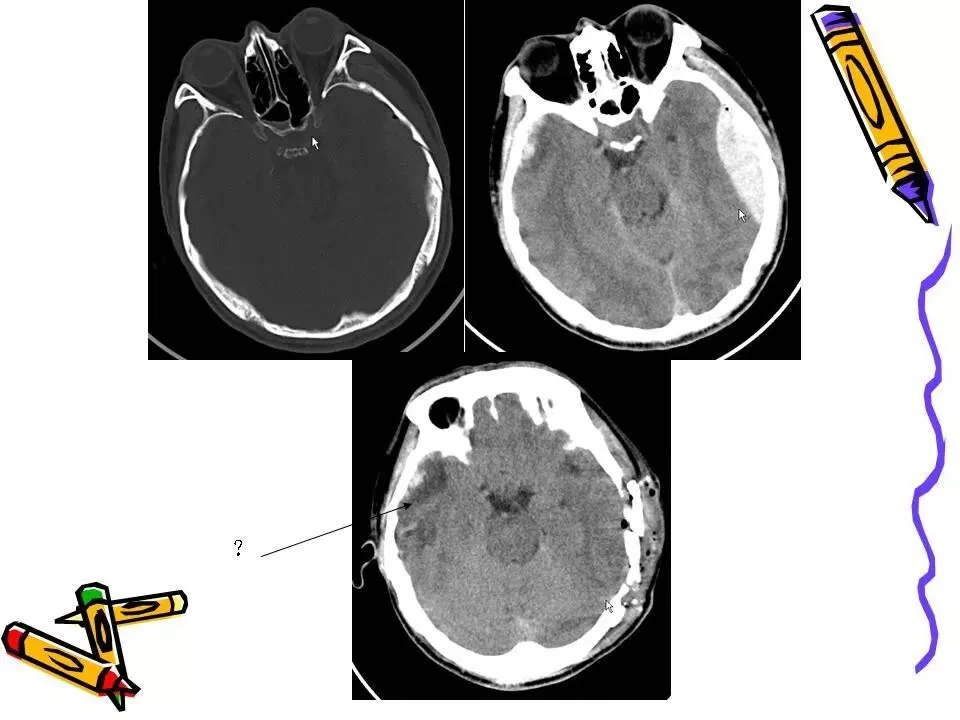

>常见颅脑外伤CT诊断(PPT)

常见颅脑外伤CT诊断(PPT)